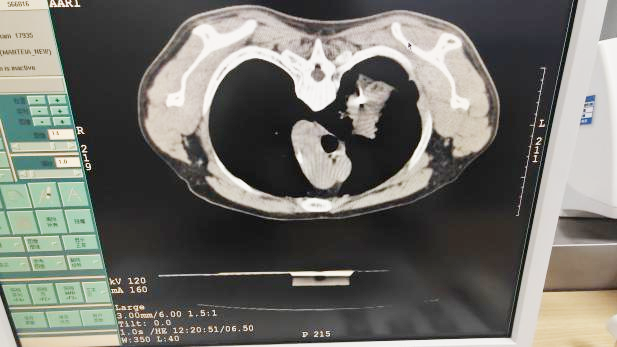

该患者肺部病灶位置特殊,不仅完全被肋骨遮挡,常规穿刺路径无法抵达,且紧邻叶间裂,操作稍有不慎便易引发气胸、出血等严重并发症,对穿刺精度提出了毫米级的严苛要求,常规手术方案风险极高。

面对挑战,呼吸诊疗中心八里湖病区徐非洲副主任医师联合放疗室罗云主治医师,依托高精度CT三维重建技术,术前为病灶完成多维度“立体画像”,经反复测算论证,摒弃常规路径,为患者个性化规划出一条既绕开肋骨屏障、又将针道全程限定于单一肺叶的“黄金穿刺轨迹”。术中在CT实时引导下,团队以毫米级精准把控完成操作,顺利取得足量合格的病理组织。患者全程生命体征平稳,术后无任何不适,病理检测顺利明确诊断。